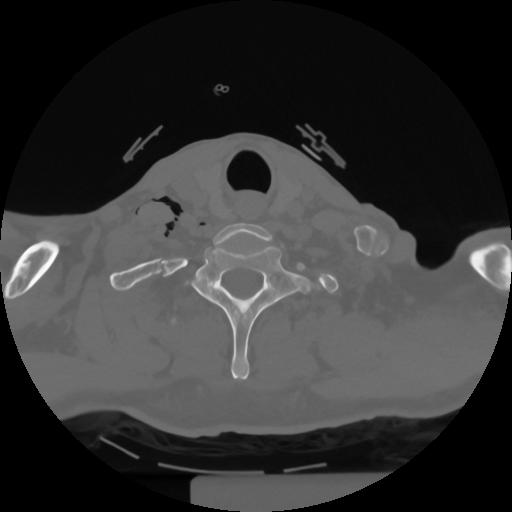

12 P.BLANDAS,,Vol,0.5,P.BLANDAS,,